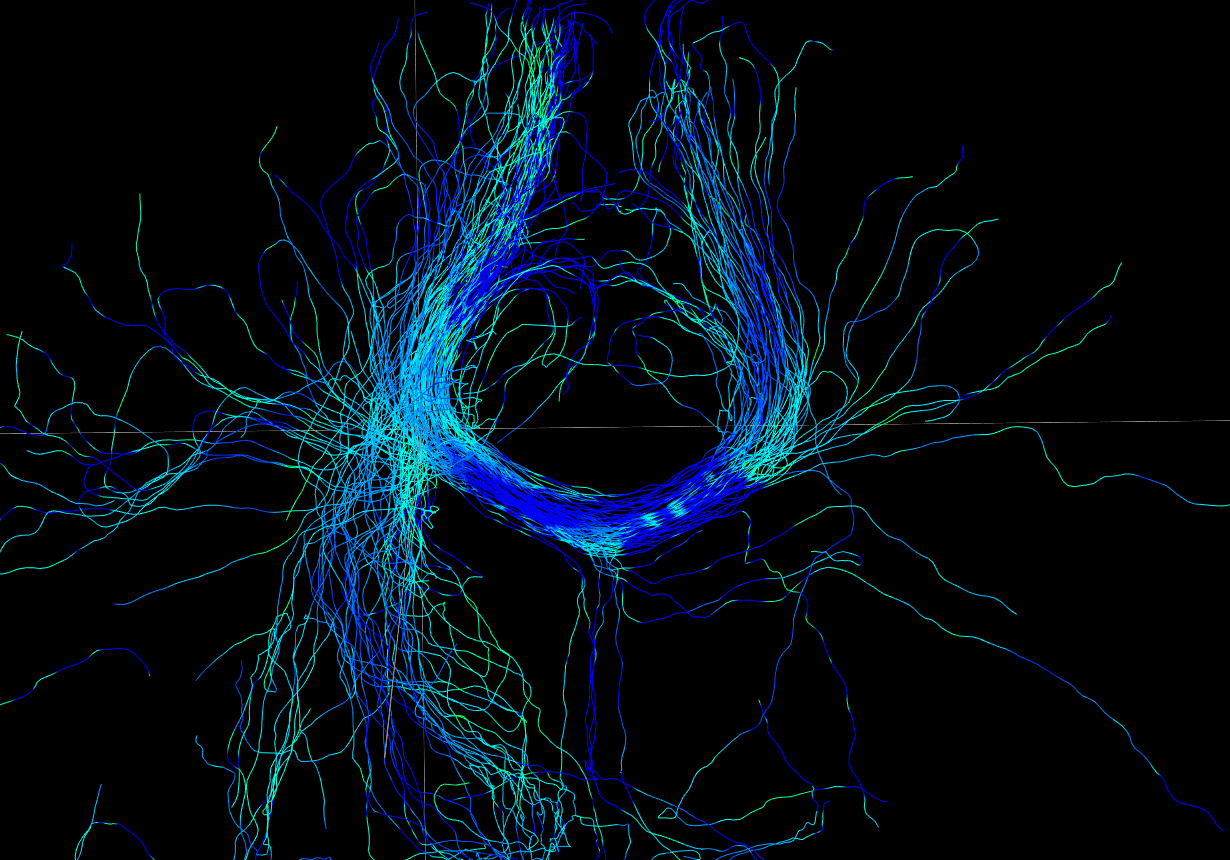

We perform whole brain streamline tractography on the estimated fODF field using mrtrix (Tournier et al., 2012) 888http://www.mrtrix.org/. The voxels with GFA larger than are used as seed voxels to generate tracts by using tckgen in mrtrix. All other parameters are default parameters in mrtrix. The obtained fiber tracts are then visualized by using trackvis 999http://trackvis.org. Fig. 14 and 15 demonstrate the tracts respectively cross two given ball ROIs. The tracts are colored by using the proposed six scalar indices. Note that the proposed scalar indices are calculated based on estimated fODFs, not based on fiber tracts. It can be seen that 1) OO is high in areas with well aligned fibers, while OD is high in crossing areas and distortion areas; 2) distortion indices are low when fibers are well aligned; 3) the total distortion index is high in areas with highly curved fibers or crossing fibers. 4) although splay, bend, twist indices may be separable (e.g., one is large while another one is close to zero) in synthetic data, in real data, these three types of distortions normally occur together, especially for bending and splaying. 5) the ROI in Fig. 14 is the crossing area of the Corpus Callosum and the Fornix, where all distortion indices have high values, especially for twist and total distortion indices. This finding agrees with Fig. 12.

ROI on OO map

OO

OD

total distortion

splay

bend

twist